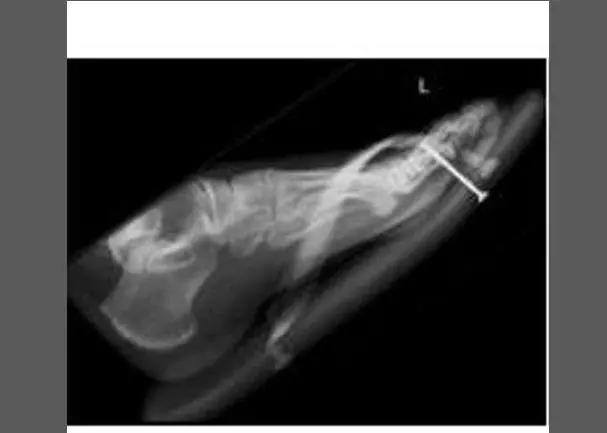

Pazze radiografie: gli oggetti che possono finire nel corpo umano

Oggetti bizzarri che hanno trovato la loro strada all'interno del corpo umano, e documentati grazie alle pazze radiografie raccolte dal dottor Frank Gaillard. Quest’ultimo ha fondato Radiopaedia.org, un sito collaborativo che raccoglie casi radiologici e articoli medici a tema.